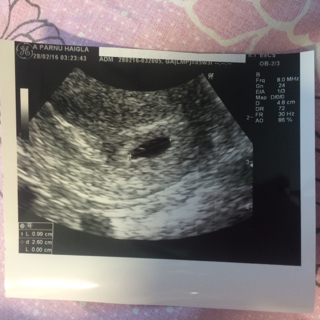

Pikkasen omaa napaa (joka on nyt jo pullahtamaisillaan ulospäin

). Täällä ei tosiaan olla pahoinvoinnilta säästytty, mutta nyt sentään jo muutaman päivän oksentamatta. Masu alkaa kasvaa ja kuukauden päästä jo rakenneultra.

15+4❤